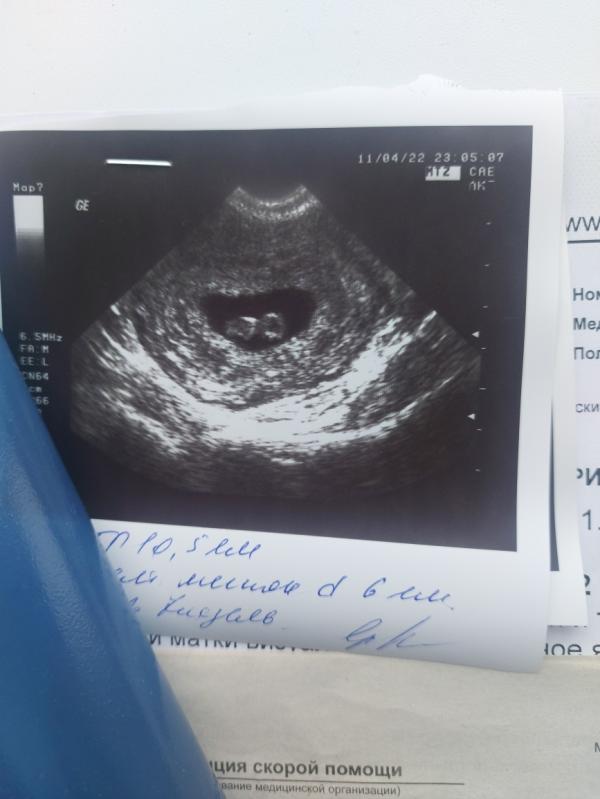

Спустился врач,начал меня осматривать.Очень быстро успокоил нас с Мужем сказал что все в порядке,и малыш развивается по срокам(никакой угрозы нет)а поясница болела,из за проблем в спине,что отдает в поясницу.поэтому такие боли.